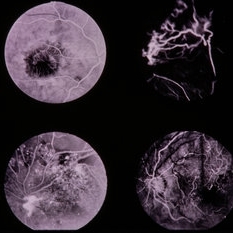

PDR

Jan 24 2014 by Howard Schatz, MD

62-year-old female. Right eye 20/25 and left eye 20/50.